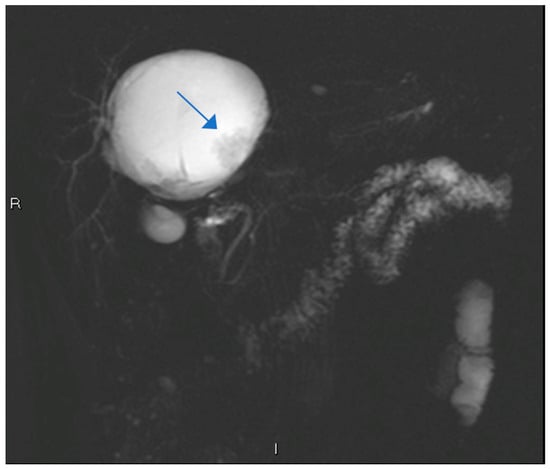

| Feature | Case 1 | Case 2 |

| Patient Demographics | 60-year-old Caucasian male | 28-year-old Caucasian female |

| Clinical Presentation | Incidental discovery of an 8 × 8 × 9 cm hepatic cyst | Presented with dyspnea, vomiting, jaundice, fever |

| Diagnostic Methods | MRI, MRCP, ERCP, histopathological examination | CT, MRI, laparoscopic liver biopsy, histopathological examination |

| Tumor Characteristics | Large cystic mass, thin walls, internal septa, papillary projections, enhancing solid components | Large lesion in left hepatic lobe, hyperintensity in T2-weighted images, restricted diffusion, contrast enhancement |

| Treatment | Cyst resection, cholecystectomy | Thrombectomy, chemotherapy, supportive care |

| Surgical Findings | Partially exophytic floating soft mass | Extensive intrahepatic metastases, vascular involvement |

| Histopathological Findings | IPNB with foci of adenocarcinoma, oncocytic appearance, varying degrees of dysplasia, mucus within cyst | Adenocarcinoma with papillary clear cell and mucinous appearance, gland ectasis, cystic or pseudocystic aspects |

| Follow-up and Outcome | Initial recurrence-free survival for 8 years, recurrence treated with left hepatectomy, patient alive at 33 months post-second surgery | Disease progression despite aggressive management, patient died from hepatic failure |